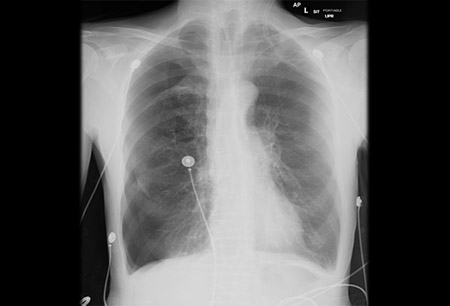

Anterior-posterior chest x-ray demonstrating a right pneumothorax

From the collection of Dr Ryland P. Byrd